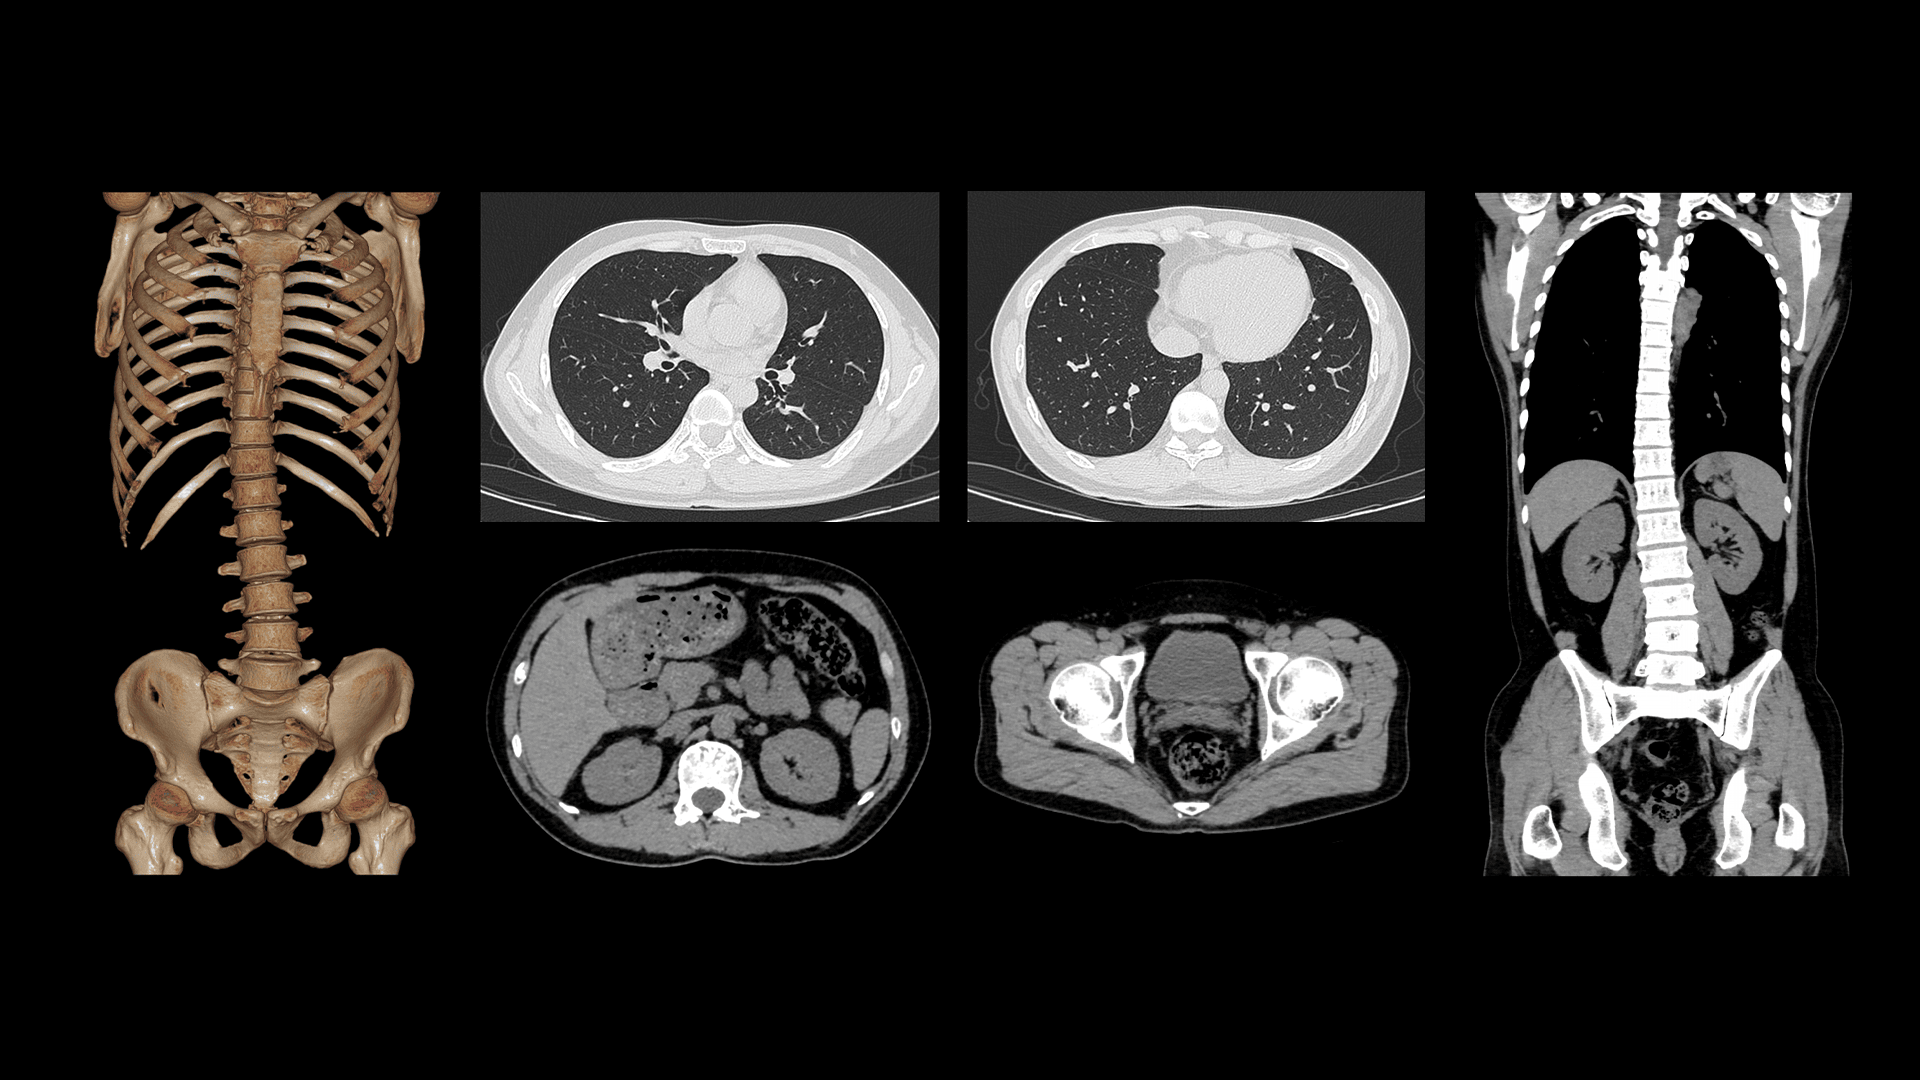

Imagistică Toracică cu Grosime de Secțiune de 0.55 mm

Detectorul Z al sistemului uCT Orion Extra oferă o grosime minimă a secțiunii de 0.55 mm, permițând o delimitare mai precisă și o vizualizare îmbunătățită a opacităților de tip ground-glass (GGO), cu definirea clară a marginilor leziunilor pulmonare.

| Parametri scanare |

Timp rotație: 0.71 s / rotație kV: 120 mAs: 30 CTDIvol: 2.9 mGy Doză efectivă: 1.5 mSv |

| Parametri reconstrucție |

Matrice: 512 × 512 Grosime secțiune: 0.55 × 0.55 mm HIR: B_SHARP_C WW/WL: 1500 / -500 |

Scanări Toraco-Abdominale Extinse

Tubul cu disipare ridicată de căldură (746 kHU/min) permite scanări continue, fără întreruperi cauzate de supraîncălzire. Astfel, uCT Orion Extra susține eficient investigații complexe, precum scanările toraco-abdominale extinse sau CT multiphasic cu contrast.

Timp rotație: 0.71 s / rotație kV: 120 mAs: 103 CTDIvol: 10.2 mGy Doză efectivă: 9.9 mSv Lungime scanare: 652 mm |

Matrice: 512 × 512 Grosime secțiune: 2.0 × 1.0 mm HIR: B_VSOFT_B WW/WL: 300/40 |

Imagistică Toracică Low-Dose la 60 kV

Pentru pacienții cu constituție slabă, tensiunea minimă de 60 kV permite reducerea semnificativă a dozei de radiații, menținând calitatea imaginii. Bronhiile principale și structurile mediastinale sunt vizualizate clar, iar reconstrucțiile MIP evidențiază precis vasele pulmonare.

Timp rotație: 0.71 s / rotație kV: 60 mAs: 210 CTDIvol: 1.8 mGy Doză efectivă: 0.8 mSv |

Matrice: 512 × 512 Grosime secțiune: 1.0 × 0.5 mm HIR: B_SHARP_C WW/WL: 1500 / -500 |